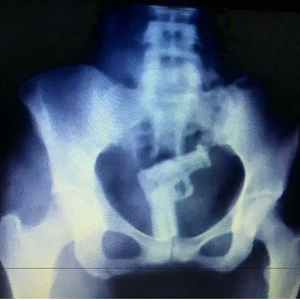

Weirdest X-ray award goes to this patient for both bravery and creativity !